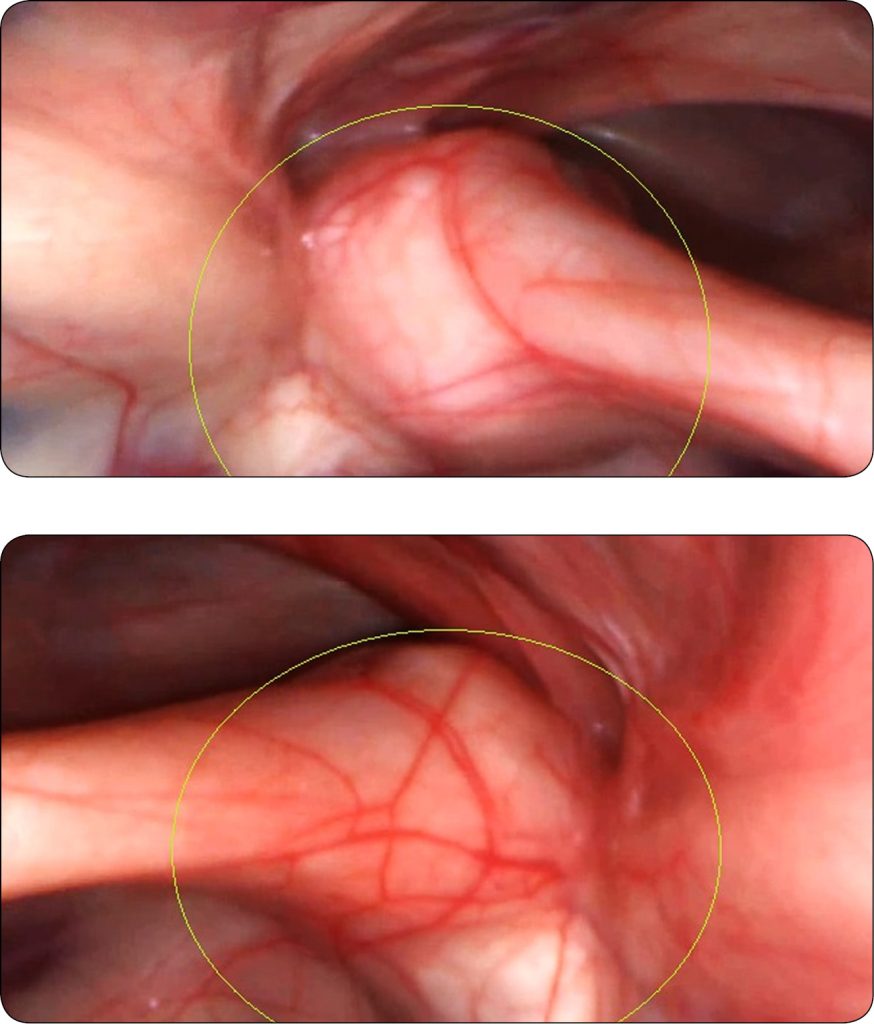

16-letni wałach szlachetnej półkrwi użytkowany w skokach przez przeszkody został przedstawiony do badania ze względu na coraz częściej powtarzające się intensywne „prychanie” (tak objaw został opisany przez właścicielki konia), pojawiające się tylko w galopie. Początkowo były to pojedyncze reakcje wałacha, którym towarzyszyło wyciąganie głowy do dołu. Na ostatnich zawodach w skokach przez przeszkody „prychanie” było tak częste, że uniemożliwiło wałachowi (mimo chęci) oddawanie skoków podczas przejazdu parkuru. W trakcie wywiadu nie uzyskano informacji o innych objawach klinicznych i problemach zdrowotnych pacjenta. Szczegółowe badanie kliniczne (przeprowadzone w spoczynku oraz po wysiłku) i ortopedyczne wałacha nie wykazało odchyleń od normy. Słyszalne w trakcie galopu „prychanie” (analiza oceny pacjenta w trakcie badania oraz dostępnej dokumentacji w postaci filmów) pozwoliło na opisanie objawu jako odgłosu pojawiającego się w trakcie wydechu, który początkowo i w pojedynczych sytuacjach dawał złudzenie fizjologicznych parsknięć. Pacjenta skierowano na badanie stomatologiczne oraz endoskopowe górnych i dolnych dróg oddechowych wraz z pobraniem popłuczyn pęcherzykowo-oskrzelowych. Endoskopowo stwierdzono obecność grudkowego zapalenia gardła, pojedyncze małe kropelki wydzieliny śluzowej w tchawicy wraz z nieznacznego stopnia pogrubieniem przegrody tchawicy. Endoskopia worków powietrznych wykazała pogrubienie i obrzęk okolicy obu stawów skroniowo-gnykowych, przy czym patologia była silniejsza w stawie lewym (ryc. 1). Bazując na uchwyconym obrazie, stwierdzono podejrzenie osteoartropatii skroniowo-gnykowej. Innych patologii nie zidentyfikowano. Wprowadzono intensywną farmakoterapię w postaci: